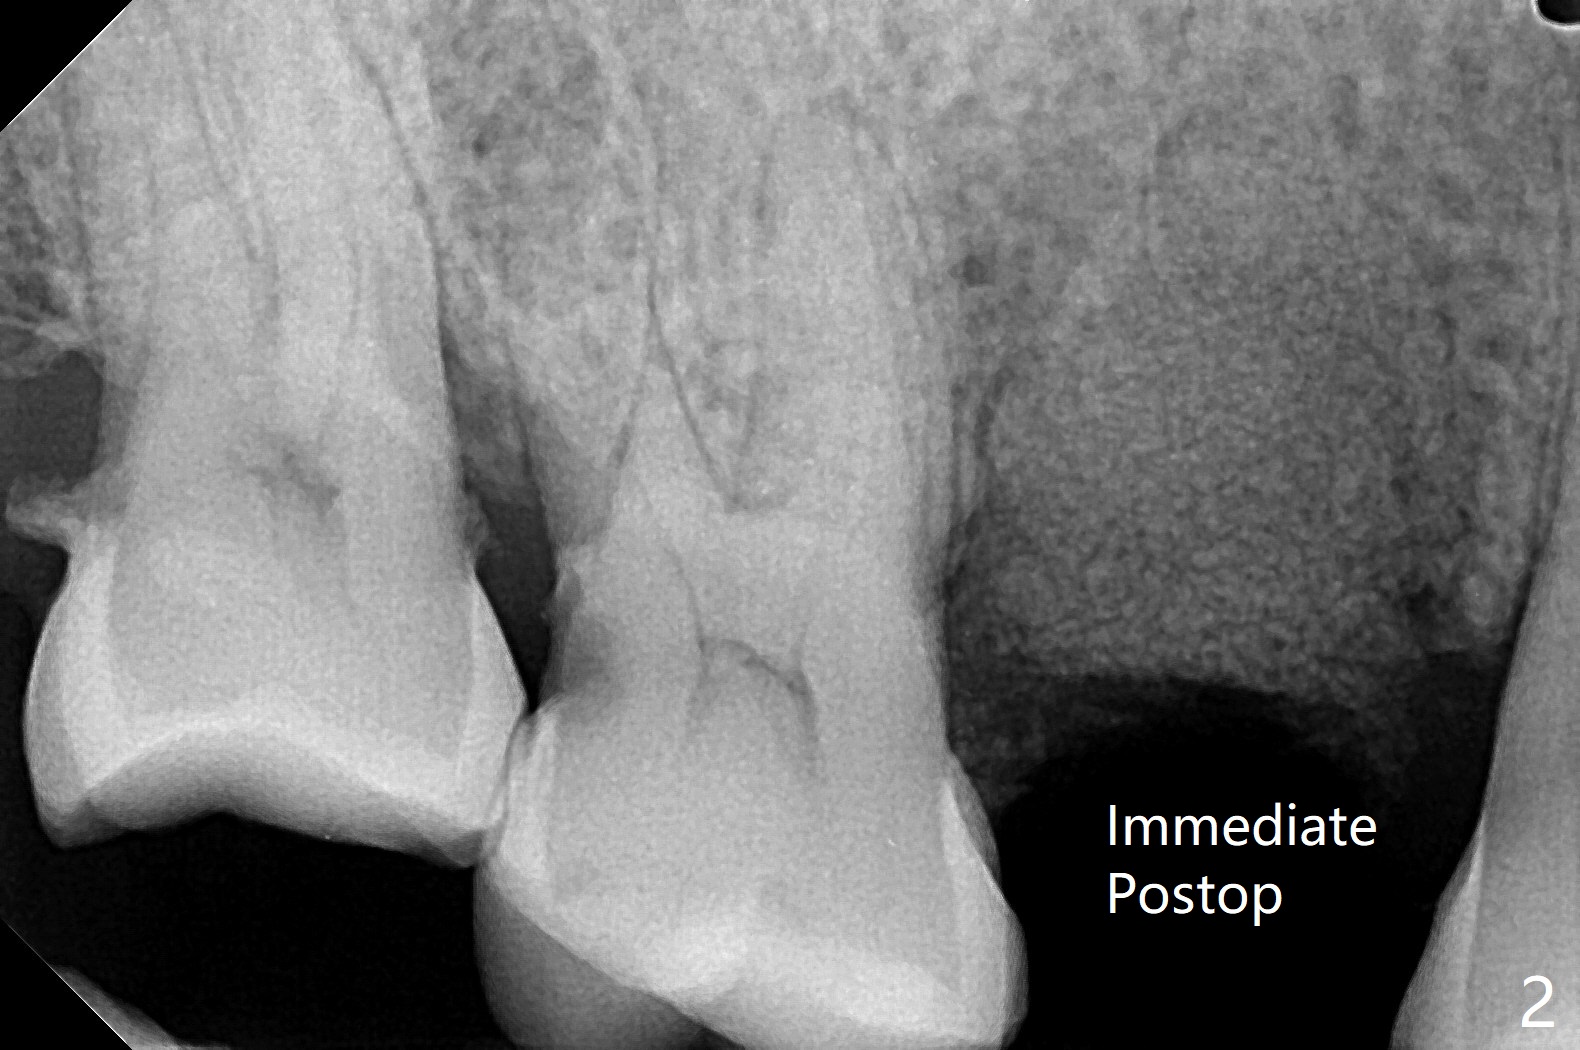

61岁女,右下六缺失,要求拔除纵裂右上五(图一:舌侧部分松动),刮除大量肉芽组织后,植入皮质骨骨粉(图二,三),覆盖6个月吸收膜,4-0 PGA 缝线,牙周敷料。